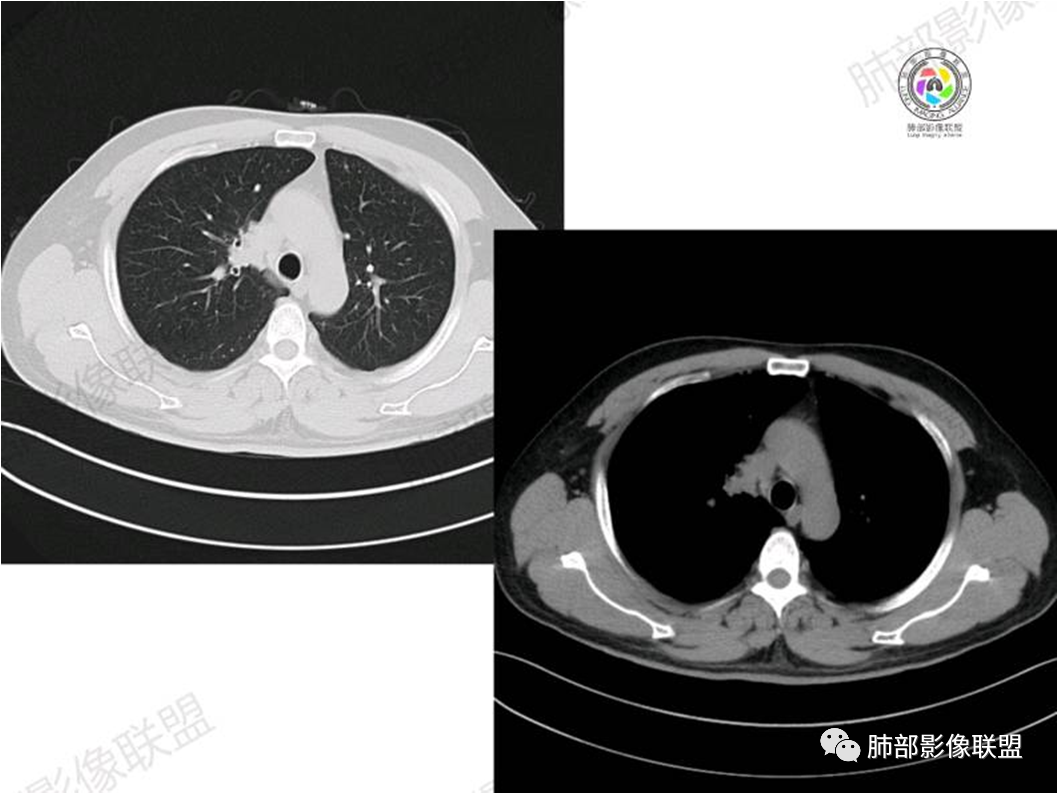

胸部CT:

①实变的出现率100%,多表现为两(89%)或单肺多发,密度均匀,与邻近胸壁肌肉的密度大致相等,少见钙化(15%),这与病灶内血管保持 完整,血供丰富,且肿瘤生长缓慢,对缺氧耐受好,不易坏死有关。边缘磨玻璃影或晕征具有特异性,其病理学基础是肿瘤细胞对小叶间隔、肺泡壁的淋巴瘤样浸润;

③扩张的充气支气管为其较特征性的表现,出现率约为89%,支气管管壁无破坏,支气管常扩张并达病灶的边缘,这与炎症性肺癌明显不同,其病理学基础是肿瘤起源于肺间质,肿瘤细胞沿着脏器解剖结构生长,周围增生的结缔组织牵拉导致支气管扩张,因而这类支气管扩张在肿瘤治疗后有时可消失;

④血管造影征是另一 点,强化的肺血管形态及走行正常,无扭曲或增 粗,其病理学基础为肿瘤细胞沿间质增生浸润,不破坏血管或支气管,病灶内肺支架结构完整,本研究发现率为75%;

⑤病灶多为中度强化,部分轻度强化;